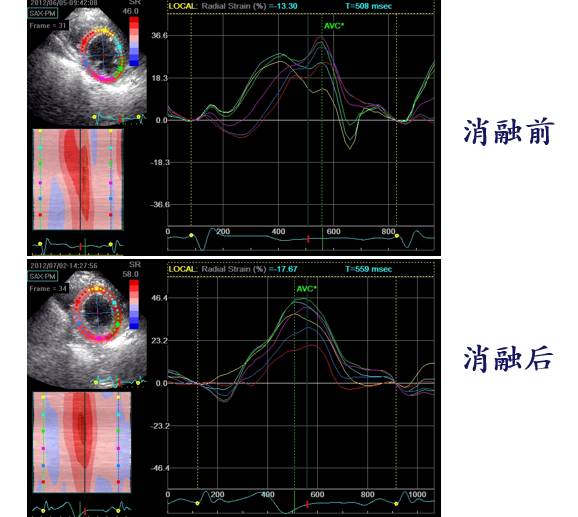

55F CAF 4 years ,CHF 6 months,NYHA III

LVED:58mm EF:28%

Ablations: PVIs 、 Roof、MI、CTI (2C3L)

6 Months Post Ablation

SHFM 消融前(上)后(下)